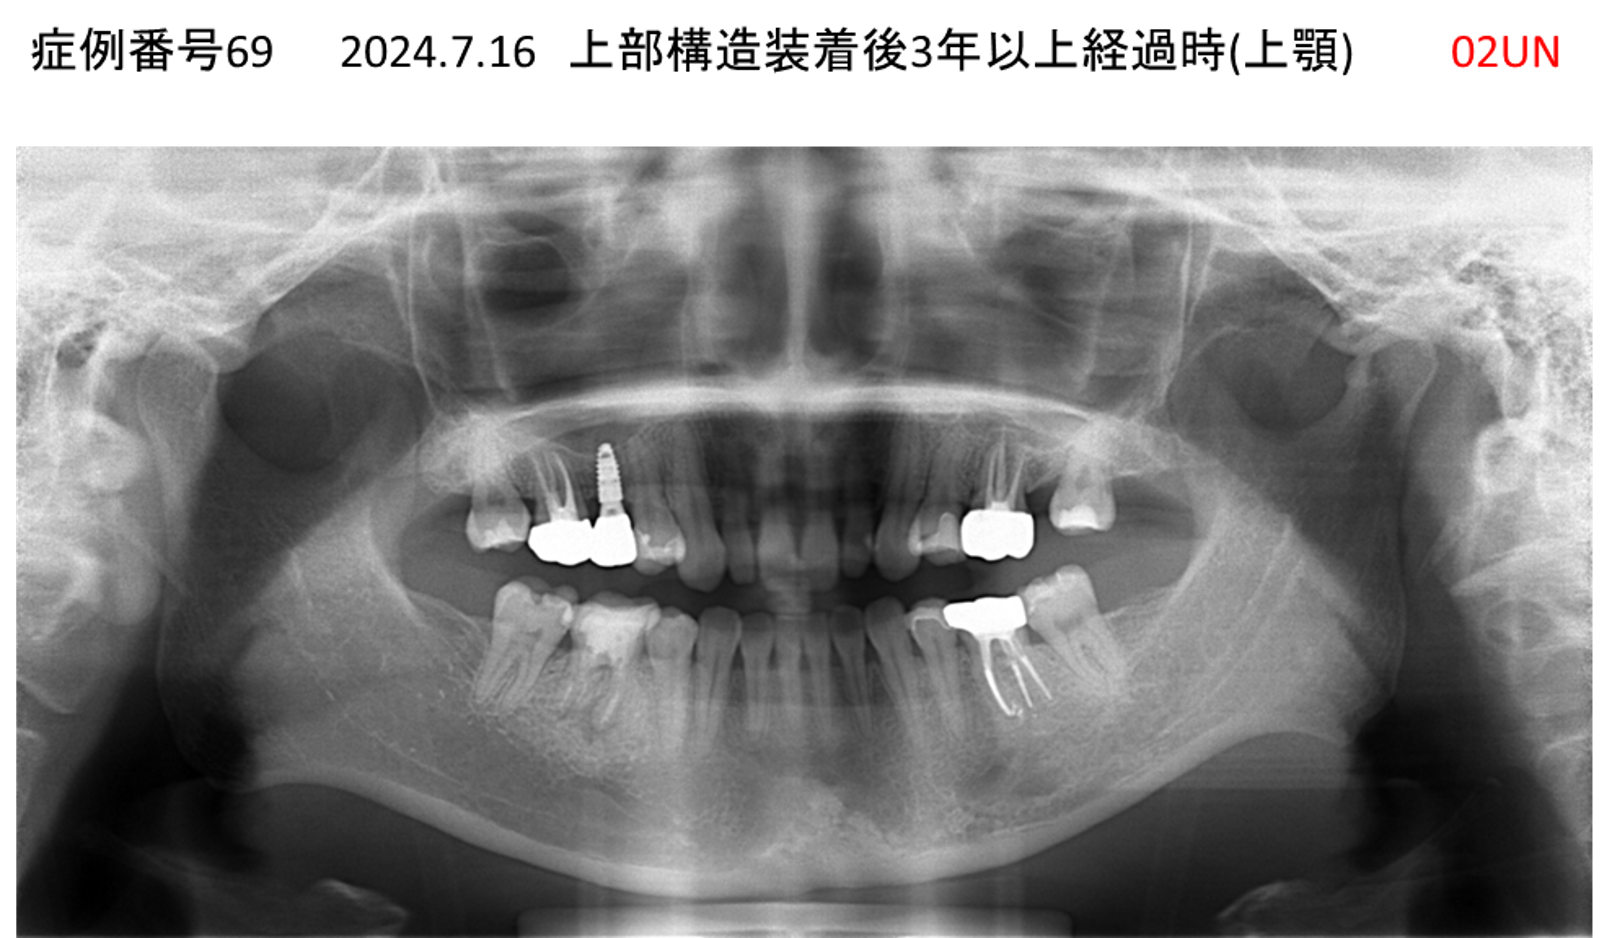

上の前歯が揺れていて痛い患者様のインプラント症例

| 治療名称 |

インプラント |

| 治療費用 |

295万円+税 |

| 治療期間 |

6か月 |

| 患者さんの症状(主訴) |

上の前歯が揺れていて痛い |

| 治療内容 |

抜歯即時インプラント |

| 治療結果 |

痛みがなく、しっかり噛める。 見栄えがとても良い |

| 治療の注意点(リスク/副作用) |

インプラントが壊れたら再治療が必要 |